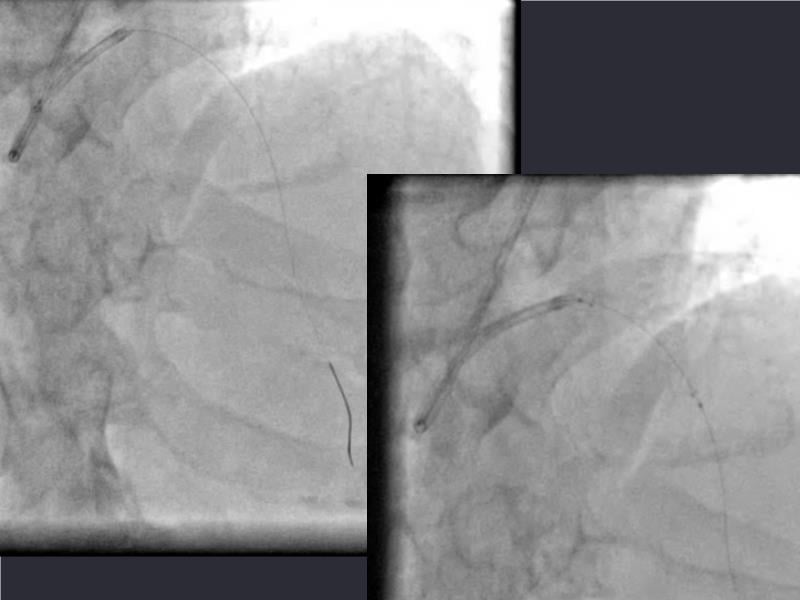

- To understand novel tools and techniques for effective management of bifurcation lesions and long diffused lesions using dedicated stenting solutions